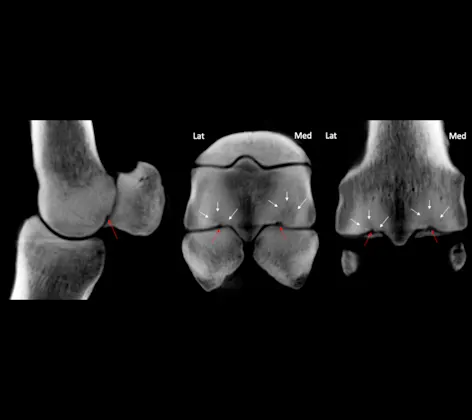

With instantaneous image acquisition and superior resolution, our MyLab 30 Gold Digital Ultrasound units provide our veterinarians with an immediate diagnosis and excellent high-quality images.